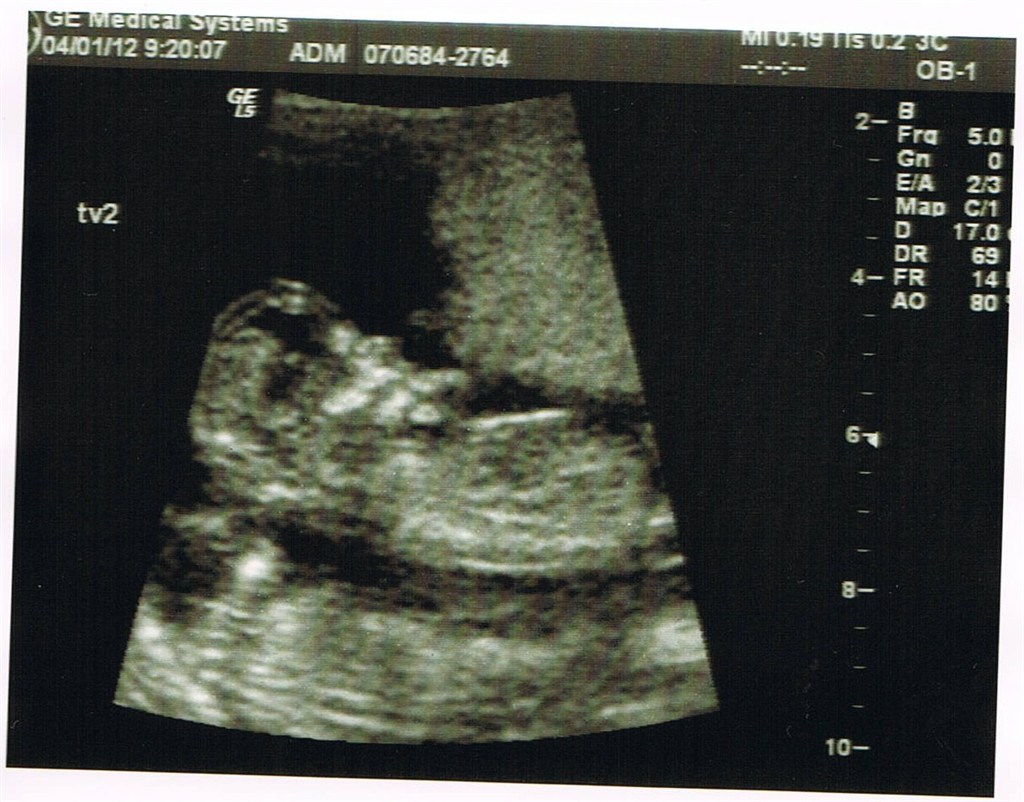

fine tal på 1:2990 på begge tvillinger og jeg blev rykket frem til at være 13+4

De fastatte nu endelig til at være enæggede tvillinger med hver deres foterhinde men samme moderkage. Dette skræmmer mig lid da det betyder scanninger hver 14 dag indtil termin og en masse undersøgelser.....